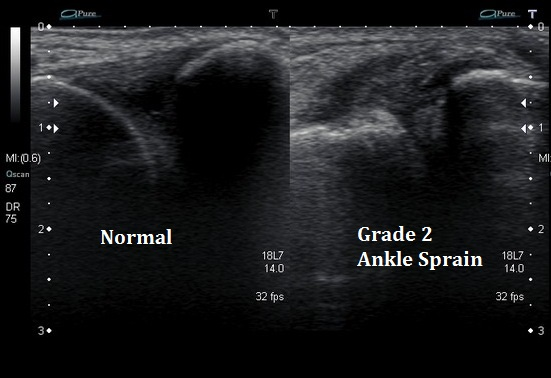

Le chiropracteur procède à des tests orthopédiques spécifiques pour évaluer la mobilité et identifier les ligaments touchés. En fonction des résultats, il pourra également vous prescrire une imagerie médicale, telle qu’une échographie et/ou une radiographie, afin d’identifier avec précision les structures en souffrance. Cela permet de visualiser les éventuels dommages ligamentaires, tendineux ou osseux, et d’ajuster le traitement en fonction de la gravité de la blessure.

• Échographie : Permet de visualiser les lésions ligamentaires et tendineuses.

Classification : Les grades des entorses

L’entorse de la cheville est classée selon trois grades, en fonction de la sévérité de la blessure et des structures ligamentaires atteintes :

• Grade 1 : Élongation ou déchirure minime des fibres ligamentaires. La douleur et l’enflure sont modérées, et la stabilité articulaire est conservée.

• Grade 2 : Déchirure partielle du ligament avec douleur, enflure importante et instabilité articulaire modérée.

• Grade 3 : Rupture complète du ligament. L’instabilité est marquée, avec une douleur et une enflure très importantes.